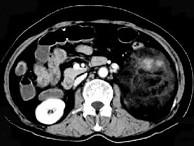

问题 女,64岁,左侧腰部胀痛,行CT扫描,下列说法正确的是()

选项 A.左肾区可见一巨大的占位性病灶,境界较清楚,胰腺尾部受压向前推移 B.该病灶密度不均匀,其内可见脂肪密度影,且呈不均匀强化 C.考虑为左肾来源的血管平滑肌脂肪瘤 D.考虑为左侧肾上腺来源的髓样脂肪瘤 E.考虑为腹膜后来源的脂肪肉瘤

答案 ABC